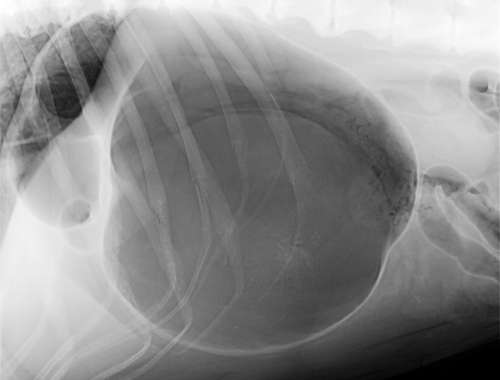

Strašák jménem TORZE ŽALUDKU

V minulém čísle jsme vám přinesli příběh se šťastným koncem, kdy fenka německého ovčáka přežila torzi žaludku. Na toto téma nám přišlo větší množství dotazů a tak nyní přinášíme téma uceleně zpracované MVDr. Milanem Štouračem. Syndrom dilatace a torze žaludku…